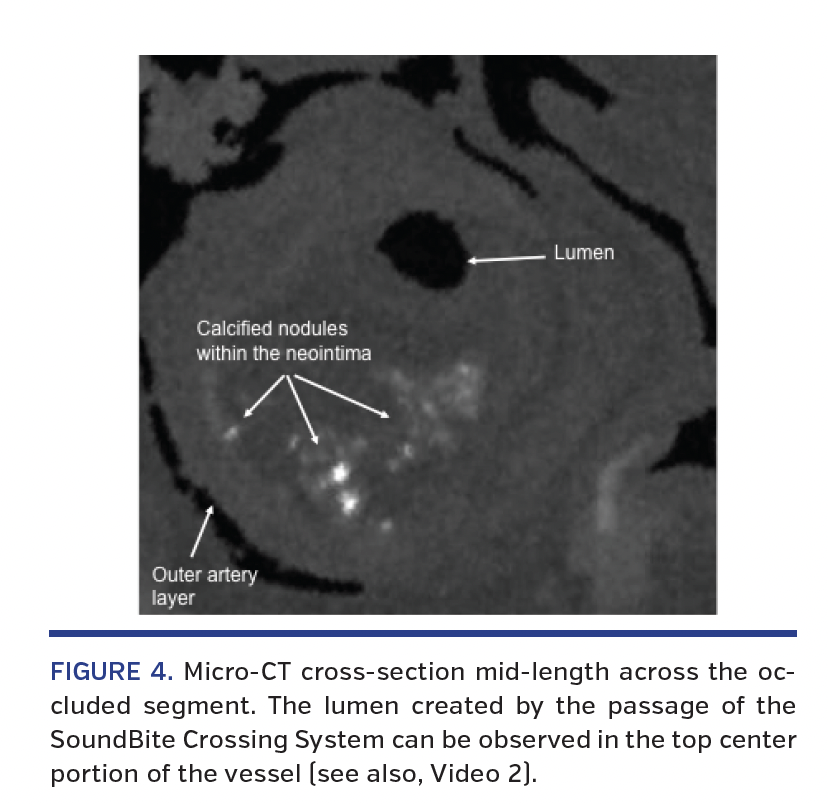

Micro-CT and histologic evaluation of occluded segment. Immediately following the procedure, the arterial segment was preserved (-4°C saline) and micro-CT and histology evaluation were performed. The micro-CT evaluation was done using an XT H 225 micro-CT instrument (Nikon Metrology, Inc) with spatial reconstruction by the CT Pro 3D software (Nikon Metrology, Inc). The images showed an area of important intraluminal stenosis throughout the middle and distal portions of the sample; however, a lumen was visible through most of the studied area associated with the passage of the ShockWire (Figure 4; Video 2). Highly radiodense material suggesting mineralization was also observed scattered along the artery, in and out of the region of interest. Most of it was small and located in the deep neointimal or medial arterial layer. Also, one major homogenous mineralized area appeared just proximal to the occlusion previously described.

Histologic evaluation was performed on thin sections (approximately 8 µm thick) from the artery prepared and stained with hematoxylin and eosin, Movat pentachrome, and Von Kossa stain. The hematoxylin and eosin stain showed tissue protruding into the lumen mainly composed of neointimal tissue, fibrosis, and area of mineralization (Figure 5). The lumen seen by micro-CT, caused by the device passage, was also found on histologic evaluation confirming a “true to true” recanalization of the occluded vascular segment. Area of mineralization evaluated by Von Kossa stain showed mineralization of the vascular segment, with the most severely mineralized area found just proximal to the bifurcation of the anterior tibial artery from the popliteal artery.